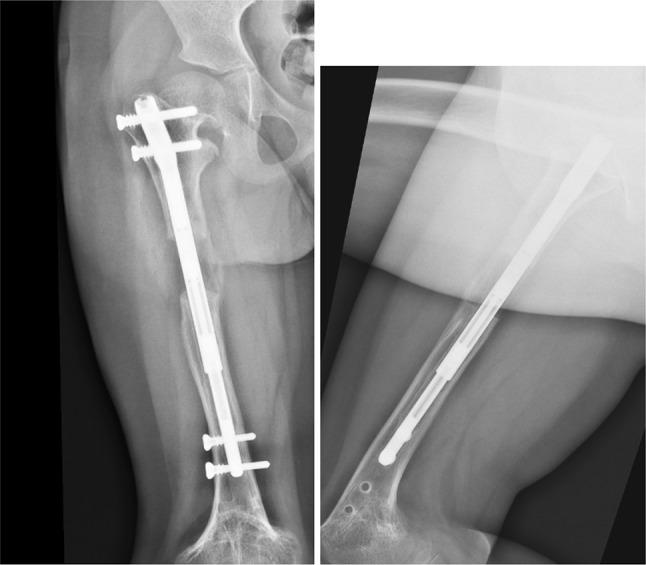

The authors present a case in which the limb lengthening has been performed in consecutive lengthening periods using the same nail. The nail was extended and retracted by altering the settings on the external remote control as well as accurately setting the rate of distraction.

After two consecutive femoral lengthening with the same PRECICE nail, the patient no longer has a significant lower limb length discrepancy and patient satisfaction was high. During this clinical case, we were not confronted with any type of complications.

作者呈现了一个病例,其中使用同一根钉子在连续的延长阶段进行肢体延长。通过改变外部遥控器的设置以及精确设定牵张速率来使钉子延长和回缩。

使用同一根PRECICE钉子连续两次进行股骨延长后,患者双下肢长度差异不再显著,患者满意度较高。在这个临床病例过程中,我们未遇到任何类型的并发症。